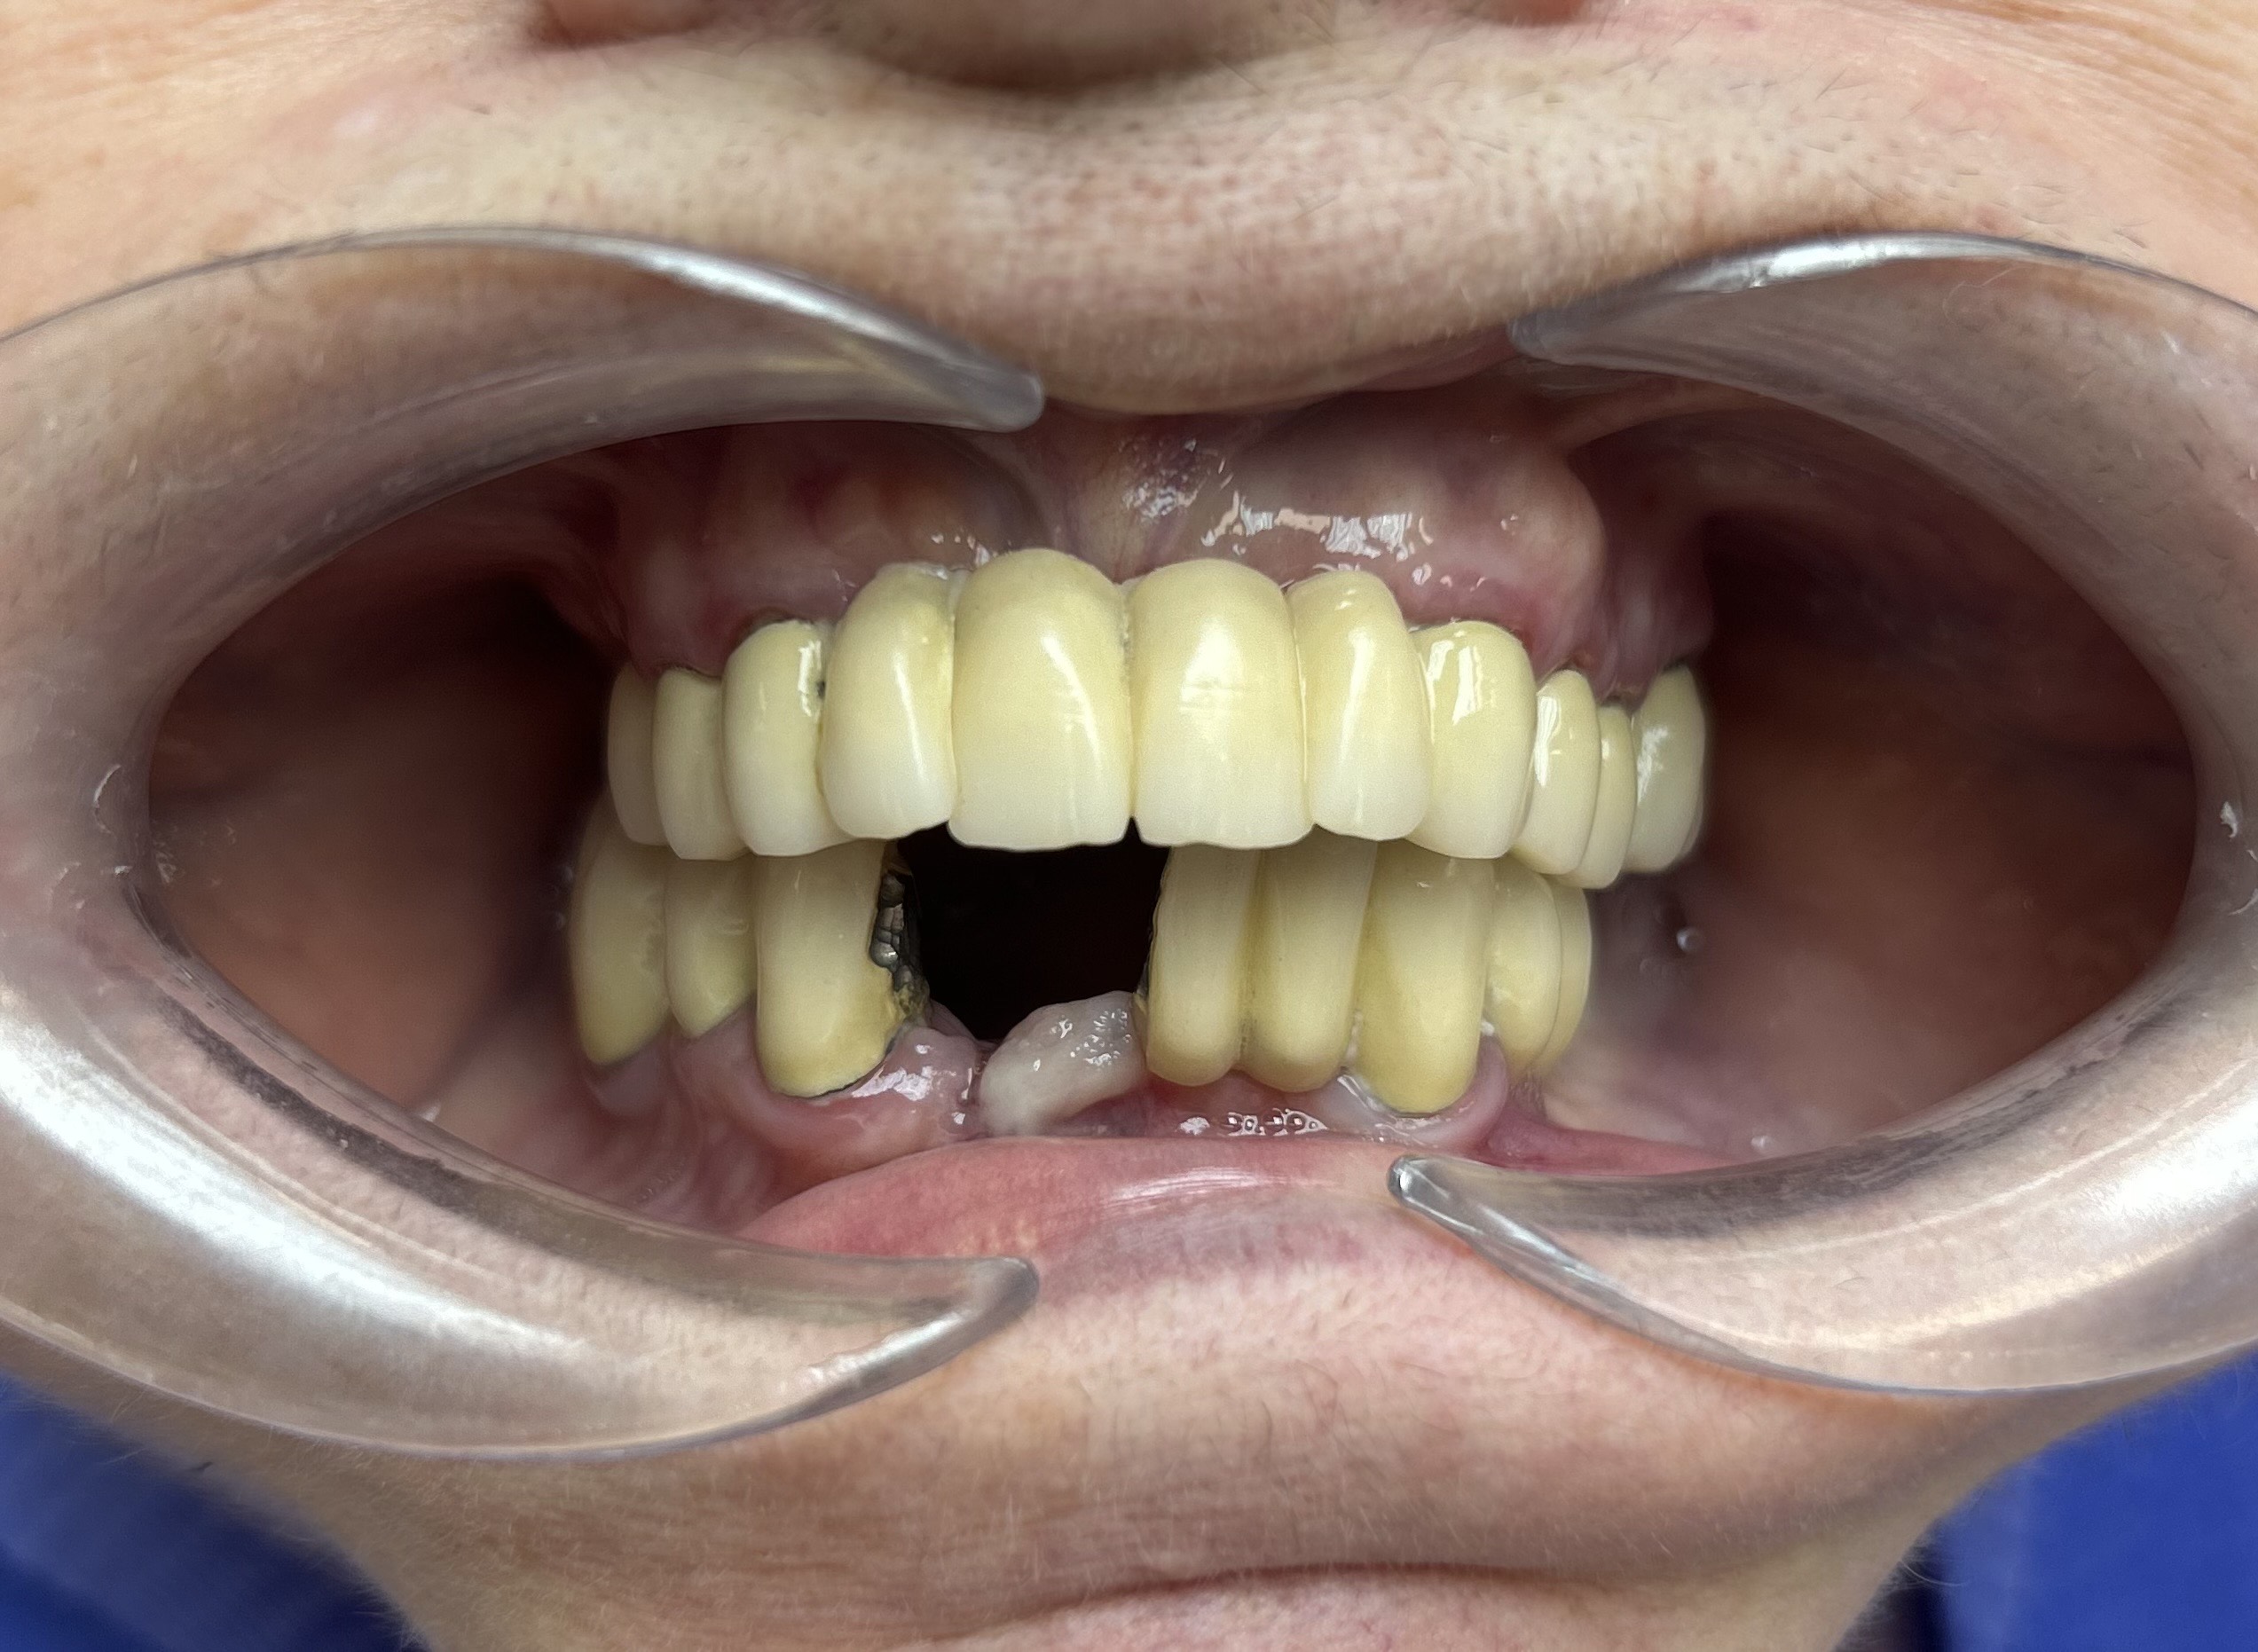

Előtte-utána: Régi alsó fémkerámia körhíd cseréje